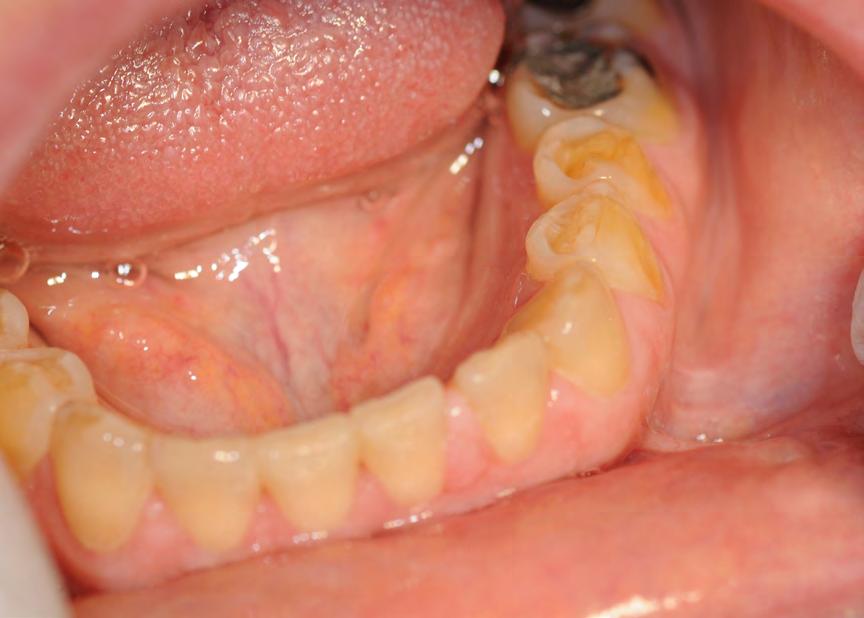

Two authors had access to the data and all information was de-identified. Study personnel made no contact with patients at any time throughout the study, and no PHI was recorded. Re corded data included diagnosis (clinical and/or pathologic), basic demographics (age, gender), and current prescription medica tions. For cases that were not biopsy-proven, the standard clinic protocol is that the clinical presentation must exhibit the charac teristic white Wickham striae for a patient to be given the clinical diagnosis of OLL or OLP (Figure 1). Any clinical diagnosis of OLL or OLP was rendered by one of four oral medicine experts in the Oral Medicine Clinic, and biopsy was performed in cases with any doubt.

Figure 1. Example of characteristic Wickham striae and reticular pattern on buccal mucosa used to clinically diagnose OLL and OLP cases. Erythematous areas also seen. Figure 2. Frequency and percent of study patients using specific medications with color-coded drug classes.